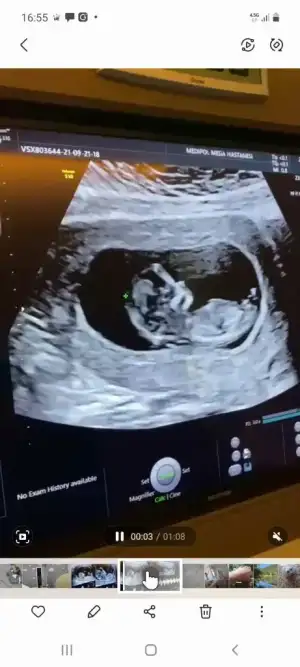

Erkek gibi sanki Emin olmadım diğerinide paylaşınKızlar merhaba. Bizde 12+2 deyiz. Sürekli hareket ettiği için en net görüntüsü bu oldu. Yorum yapabilir misiniz. Teşekkür ederim![]()

Bir gün önceki de bu şekilde. Uyuyordu sanırımErkek gibi sanki Emin olmadım diğerinide paylaşın

Kiz gibi geldiBir gün önceki de bu şekilde. Uyuyordu sanırım![]()